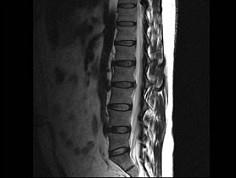

问题 男,45岁,背部隐痛半年余,请结合影像学检查,选出最可能的诊断 ( )

选项 A、椎间盘突出 B、神经根鞘囊肿 C、硬膜外纤维化 D、椎管内肿瘤 E、椎间盘炎

答案 A